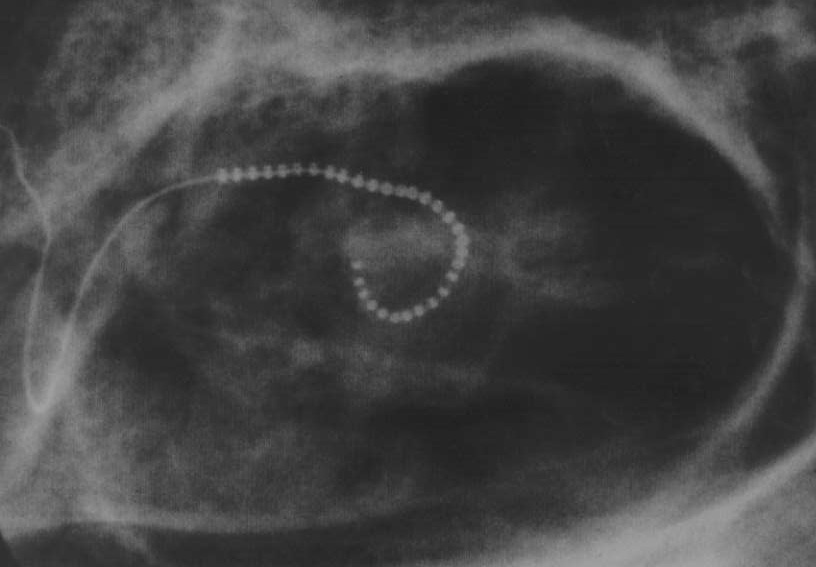

チルドレンセンター(東京)所長 東京医科大学名誉教授 舩坂宗太郎 ![]() ただいまご紹介いただきました舩坂です。わたくしの話をはじめる前に、服部先生のご講演に一つ追加させていただきたいと思います。 これは日本の厚生省の官僚主義的やり方で、結果的には私たち、ろうの方々、わたしたち手術を行う耳鼻科医が損をしている。それは・・先ほど服部先生がおっしゃられたN24という人工内耳がございます。これは、三つ音声を処理する方式が含まれている。そして、一つは今までのやりかた。もう一つはACEと書きましてエースと呼ばれているもの。それから、もう一つはCISと呼ばれる、シスと呼ばれている。 使われた方は、もう今までのやり方よりはACEないしはCISの方が圧倒的に言葉がわかるという風に、皆さん世界の方々はおっしゃっておられる。ですけど、日本では一番新しいN24が入りましても、厚生省の方でCISとACEを使うことが禁じられております。事実私どもが機械を使うためのソフトウエアを入れますディスクにはちゃんとロックされていて、シスとエースを密かに使おうと思っても使えないようなソフトしかわたしどもには来ていません。 ですから、私はかんかんに怒って、厚生省と交渉しているところなんですが、厚生省は厚生労働省になりまして、どうも見てますと、労働省の人間の方が頭がいい。厚生省はがたがたしていてこっちの言うことを聞いてくれない。それどころじゃあない、おれたちが首になりそうだという雰囲気さえ感じられる。ですから、大変難しい交渉になると思いますが、わたしの予想では来年か再来年には日本でもCISないしACEが使えることを期待しています。 以上だけ、追加させていただきました。服部先生、どうもありがとうございました。いよいよ、わたしの話に入りたいと思います。今要約筆記の方が次々と私の話の内容を示して参りますので、それをわたしは読むことにします。どうぞ出してください。 先天聾に対する人工内耳の効果は素晴らしく、舩坂が設けているチルドレンセンター(東京)では、いま学齢期に達した11名全ての子が普通小学校に通っています。 (というのはまだ四月にならないと通わないわけですが、東京近辺、中部地方は知らないが、11月に教育委員会が難聴児ないしは障害児を振り分ける。幸い、チルドレンセンターで育ちました難聴児はすべて普通小学校へOKが教育委員会から出ていますので、この4月からは全員普通小学校へ通えます。中部地方では存じませんが11月には教育委員会の振り分けが行われると思います。) この人工内耳は、オーストラリア、メルボルン大学の耳鼻咽喉科クラーク教授によって、開発されました。長身で温厚なクラ−ク教授は、私の最も尊敬する学者の一人です。 (先ほどの写真では全身の姿はなかったと思いますが、長身(背の高い方)で、写真を見てわかるように温厚なクラーク教授です。) クラーク教授からは、日本で最初に人工内耳を行い、その普及−たとえば健康保険適用、地方自治体の経済的支援など−に努力し、言語訓練を含めた先天聾幼児への適切な応用などを評価していただき、メルボルン大学人工内耳研究所の名誉研究員に指名されました。この名誉研究員は、旧西ドイツハノーバ大学レーンハルト教授と世界でただ二人だけです。大変名誉なことと感激しております。 (人工内耳をつけても身体障害者手帳の書き換えは必要ない、そのままもってらっしゃいと言って、難聴では2級ということになって、ある程度地方自治体からも援助が出ます。そういう風にして小さいお子さんのもってらっしゃる家庭はある程度経済的に助かっていると言うこともあります。) 人工内耳は先天襲の幼い子には、きわめて有効な“正常な聞こえの取り戻し方法”です。論より証拠、先天聾の赤ちゃんを二人かかえながらも、ともどもに頑張り、いま姉は普通小学校に入れ、妹は普通幼稚園に通っているというお母さんの涙ぐましい手記を、私の話の前に、まず掲げましょう。 以下は伊藤里子(伊藤麻奈ちゃん、奈恵ちゃんのお母さん)が綴った手記です。 (二人とも先天聾です。私ども耳鼻科の医者からするとこうした例は少ないんです。お姉ちゃん、ないしはお兄ちゃんは先天聾だけどその後に生まれてきた子は正常というのが圧倒的に多い。ですが、伊藤里子さんの場合は麻奈ちゃん、奈恵ちゃん、お二人とも先天聾で生まれてしまった非常につらい立場です。) 先天聾姉妹が自由に会話できる! 伊藤麻奈・奈恵ちゃんのプロフィール 姉の麻奈ちゃん、一九九三年十月生まれ。先天聾。一歳五カ月で補聴器装用して言語訓練したが、言葉の伸びは不充分。 (補聴器装用については、これは大変有効だった。言葉としては補聴器は役に立たないんですが、世の中に音があるということが何とかわかる。補聴器をつけて太鼓をたたくとか、タンバリンをたたくとか、トライアングルでチンチンと聞かせると言うことが大事なことなんですね。) 一九九六年九月(二歳十一カ月)、人工内耳の埋め込み手術し、チルドレン・センターで言語訓練。今は自由に会話でき、小学校一年生で成績優秀。 妹の奈恵ちゃん、一九九五年五月生まれ。先天聾。一九九七年十二月(二歳七カ月)で人工内耳の埋め込み手術を行い、チルドレン・センターにて言語訓練、現在日常会話が可能で普通幼稚園に通園中。 (関東地区は少子化のために、一つの幼稚園が受け持つ人数が少ない。もっと理想的な幼稚園では13人しかいないもんですから、先生が非常に丁寧に話してくれる。人工内耳の子も喜んで幼稚園に通う雰囲気。これはわたしの意見ですが、そういうお子さんをクラスメイトに持っている幼稚園の他のお子さんにとっても大変いいこと。障害を持っているお子さんにどう接していいか、つきあいの中から自然に覚えていく。昔は向こう三軒両隣というように、隣同士のつきあいが非常に緊密だった。大人が子どもをしつけたわけですが、今の東京ではバラバラになって、大人が子どもをきちんと障害者にどう接するか、教え込むことがなくなった。子供たちは子供たちで覚えていく。非常に自然で、わたしはよいことだと思います。) ――――――――――――――――――― この春、長女麻奈がピカピカの−年生になりました。この子が誕生して六年五カ月、随分といろいろなことがありました。聾だと知らされたあの頃、長男と並んでランドセルを背負って地元の小学校に通うことなど、叶わぬ夢と思っていました。 人工内耳の情報がほとんどなかった五年前、私達夫婦は麻奈を連れ幾つかの耳鼻科を訪ね、人工内耳のことを伺いました。先生方は「まだ実験段階、やるもんじゃない。」の意見でした。どうしようもない気持ちで諦めていた私たちでしたが、ある日夕刊の一面にチルドレンセンターでの舩坂先生の記事をみることができました。 「子供にもできるようになったんだ!、子供にもやってくださるお医者様がいるんだ!」と、あの時の感動は今でも覚えています。 こうして私たち親子は人工内耳と出会うことができました。いまでは考えられませんが、あの頃は子供の装用に消極的な医療機関が多かったように覚えています。しかし、舩坂先生は適切な説明とアドバイスをしてくださいました。また、入院後東京医科大学病院の担当先生は、親切に気を使ってくださいました。進むべき道は、私達夫婦にしっかり任されたと感じました。そして、その決断は間違っていませんでした。いま、手術を受ける決断をして良かったと自信を持って思い、感謝しております。新しいことをはじめる勇気と努力、信念を貫き通す勇気を、舩坂先生に感じます。 普通小学校に通うことがすべて良いと思っている訳ではありません。けれども“重度の難聴児も、地域のお友達と一緒に学校の先生の声を聞いて勉強することができる”という選択を与えてくれたのは、舩坂先生と人工内耳だと信じています。そして麻奈を導いてくれたのは、舩坂先生をはじめとするチルドレン・センターの皆様です。本当にありがとうございました。まだまだ先は永く険しかろうと思いますが、一生懸命頑張って参りますので、これからもよろしくお願い申し上げます。 ――――――――――――――――――― この伊藤麻奈ちゃんのお母様の手記をご覧になって、どのようにお感じになられましたか? おそらく「先天聾でも人工内耳で普通小学校に通うことができるようになるのか」と思われたことでしょう。このように人工内耳は素晴らしい聾の治療法なのです。もっと普及されるべきだと、私は思っています。 このほか、栃木県の観あすか、あやかちゃん姉妹−この姉妹は県の絵画展覧会でともに一位を受賞しました。 (もう時間がだいぶたってますので、ある程度医学的な事を説明しても、お母様はお怒りにならないと思いますが、実はお母様は苦しんでおられた。でも、もう子どもをおろすには遅すぎたので、そのまま出産された。そしたら、双子でしかも二人とも先天ろうで生まれてきた、という非常にお気の毒な方なんです。ところがこういうお子さまは、耳が悪いために耳を通して言葉を覚えることができないだけで、他の能力はむしろ優れていることが多い。わたくしの周辺でも、この観さん、お二人とも絵がうまく、栃木県で行われた小学生の美術展で、二人とも1等賞をとった。) 茨城県の坂場友紀ちゃん−この子は1歳6ヵ月のとき髄膜炎という怖い病気で、耳がまったく聞こえなくなったのです−しかし人工内耳のおかげで、いまバレーを習っています。 そして3歳6ヵ月のとき友紀ちゃんと同じように髄膜炎で全聾となり、お母さんとは読話でコミニケーションが充分にできていた南雲麻衣ちゃんも、小学校ではさすがに読話では無理で、7歳3ヵ月のとき人工内耳を付けて、話が自由にできるようになり、いまではクラスの人気者になっています。 (観さんたちの場合はうまくいったケースです。人工内耳をつけて会話ができるようになって、ところがどうしても聞き取れる音程に幅がある。ちょっと複雑な曲になると、普通の方より物足りなく音楽を聞いてしまうんです。それを自分の頭の方で補っていこうと・・子どもはそうは考えてないんでしょうけど、とにかく自分の頭で補うんだという無意識の気持ちがあって、今ピアノを習っている子がいます。それからバレエを習っています。そういう話が私どものところにお母様から報告されるたびに、私は大変良かったなあと思っています。) このように、人工内耳で先天聾の幼児でも会話できるようになりました。すなわち、先の伊藤里子さんの手記にあるように、二〜三歳で人工内耳を付け、乳幼児、両親、私達が一体となって努力し、ちゃんと言葉の訓練を行えば、必ず会話能力が身につき、普通幼椎園や普通小学校に通えるようになったのです。もちろん、後天聾ではもっと年長児でも人工内耳手術は間に合います。 この素晴らしい人工内耳は二十世紀の画期的な医療の進歩といえるでしょう。しかし、わが国では人工内耳の乳幼児への効果はまだあまり知られていません。その実施にも他の先進諸国と異なって、いろいろ問題があります。いまのわが国は、福祉よりも我執に囚われた社会風潮が目立ちます。欧米諸国や台湾・韓国などを視察したとき、この風潮に加えて、厚生官僚の時代遅れで不合理な医療統制、真の難聴医療に目を背けた日本耳鼻咽喉科学会に、寂しいものを感じさせられました。 私は、有名な世界最強の旧日本海軍戦闘機“零戦”を設計された故堀越二郎氏の主治医に昭和五十年になりました。そして、いろいろお話しを伺う機会を持ちました。そのなかの、「模倣と小細工のみでは零戦は生まれなかったであろう。独特の考え方と哲学、そして日本人の血の通った飛行機を作る意思で可能となったのである。」、「大きな仕事をなしとげるためには、労苦と心配がきわめて強い。長期にわたる努力が必要である」、「見通しのない政策、誤った政策しか持てない指導者は国を滅ぼす」は、なぜか今でも忘れられません。掘越二郎氏のお人柄を偲ばせる素敵なお言葉です。 さて、人工内耳の説明の前に、ヒトはなぜ自然に話し言葉を幼児時代に覚えてしまうかをお話しします。それは、耳が母親や家族・友人からの言葉の特徴を詳しく分析して大脳に送り、アクセント・イントネーションから始まり、単語や文の理解そしてイメージを浮かべるという大脳の「言葉を理解し記憶する神経の働き」を幼いうちに完成させるからなのです。この言語を覚える能力はヒトだけに具わったもので、正常な耳があってこそ発達するのです。(例えばワンちゃんがいると言ったとき、犬のイメージがぱっと頭に浮かぶ)この能力は3歳を過ぎると、脳の神経ネットワークが巧くできず、会話を身に付けることはできません。幼いうちに人工内耳を付けることが必要です。 高度の耳の障害では、音が聞こえないだけでなく音の聞き分けもできません。言葉の聞き分けができないと、音を大きくするだけの補聴器では話の聞き取りはできません。1994年のイギリスの研究で、補聴器の限度は70デシベルまでの感音難聴というのが明らかとなっています。逆に考えると、70デシベル以上の難聴では、最新のデジタル補聴器でも言葉を覚えることはできないということになります。また事実そうなのです。 (デシベルという単位はご存じですね。若い人がかすかに聞こえる音を0デシベル、耳元で大きな声で怒鳴って聞こえる程度が100デシベル、その間を100等分して30デシベルとか35デシベルとか・・。) 人工内耳は、蝸牛に入れる電極、音分析器(スピーチ・プロセッサ)から成り立っています。言葉も含めて人工内耳で受けた音は、スピーチ・プロセッサで分析され、無線で蝸牛のなかの電極に送られます。こうして蝸牛の電極は、言葉や外部の音に応じて、聴神経をいろいろに興奮させます。この聴神経の興奮が大脳に送られ、大脳は言葉や外部の音を聞き分けます。すなわち、人工内耳では補聴器が役に立たない高度難聴や聾でも、言葉や環境音の聞き分けができるのです。 (もうみなさま人工内耳はごぞんじかとは思いますが、一応どんなものであるかを・・お見せします。) (ここが耳ですね。私ども手術をしまして、この蝸牛のところまで到達して、この蝸牛の中に入れられた電極は、頭の横っちょにくっつける外部アンテナでいろんな信号を操作される。で、頭の蝸牛の中の神経を興奮させる。頭に昇って、言葉を理解する。結果的には外部アンテナとマイクロフォンとそれからスピーチプロセッサといってポケットに入る大きさです。いろんな外界の音を分析してくれるスピーチプロセッサというものです。これはわたしどもが手術で埋め込む電極です。この先端の細いところが電極、これは、側頭骨、皮膚の下の骨に半ば埋められるという形になってます。これで人工内耳についておおよそおわかりになったと思います。) ![]() (そうしますと、これは・・ここにずっと蝸牛がございまして、その中に電極がしゅーっと。だいたいこの辺まではいる。それ以上奥には入らない。いまは改良型の電極があって最近の一番進んだ電極では少なくともこの辺までは入るようになった。そうすると刺激される聴神経の範囲が広くなりますので、より言葉がわかりやすくなる。短期間の訓練で会話ができるようになる、という可能性も大きくなってきた。) ![]() (現実に、電極を入れました後、レントゲンを撮ってみまして、これは、ごく最近のものでは無いが、これは手術がうまくいかなくてここまで入らなかった。わたしが手術してこんなこというのも変ですが、手術としては完璧なケースです。手術後レントゲンをとりまして、こういう風であると・・。) 人工内耳装用乳幼児は耳つまり聞こえのみで訓練するのが原則で、補聴器を付けた難聴幼小児の訓練つまり読話併用で行うのとは、まったく違っています。先天聾の乳児は視覚にたよる癖が付いています。視覚では、会話は覚えられません。ですから、子供が動作や手真似で要求したら無視するよう親に指導します。その代わり、言葉で要求したときは、大袈裟に褒めてすぐ叶えてあげるよう指導します。そして、ほかの子供達とも付き合えるように躾けていきます。 そのうえで、なるべく早く普通の保育園・幼稚園に行かせます。幼児にとっては、子供同士の付き合いと他の子供から言葉を覚えることも大切だからです。 (こういう子どもたちは耳が聞こえないので、特にお母様の顔を見て、お母様の口の動きを見て言葉を判断する癖がついています。ところが、読話だけでは言葉は覚わりません。むしろ人工内耳をつけた場合は読話は一種の弊害すらある。耳を使って言葉を覚える妨げになる。人間一点に注意を集中するのと、こっちとこっちに注意を集中するのでは注意の集中の仕方が違います。1点に注意を集中していただきたい。) チルドレンセンター(東京)では、いま18名の人工内耳装用乳幼児の言語習得訓練を行っています。学齢期に達した幼児8名は全て普通小学校に入れ、今年4月には3名全てが普通小学校に入れることになっています。これは世界水準を上回る成績で、スタッフや家族とくに母親の努力の賜物です。 (もうひとつあえていえば、私が慎重にケースを選んでいる。自信を持った施設では、ある程度悪条件かなと思った子でも手術するんですね。そういう子だとあるいは言葉を覚えられないかもしれない。これはあまり威張れたことではないんですが、日本では慎重に子供を選んでいかなければいけない段階なのです。) ともあれ、この訓練から得られた印象をまとめてみますと、次のようになります。 1、先天聾に対し、人工内耳は2歳台までの装用が好ましい。 2、人工内耳を付けたあと三カ月で五十音が発語できる児は、一年で会話可能となる。 3、先天聾では、生後一年までに補聴器を付けて音を聞かせ、その後に人工内耳を装着するのが好ましい。 4、生後一年半以内になった後天聾は先天聾に準じて対処する。 5、生後三年半以後になった後天聾は六歳以後でも人工内耳は有効である。 6、きちんと躾をし、そして浴びせるように話しかける母親の子は言葉の発達が早い。 最後の項目6、は言われてみれば当たりまえのことですが、案外知られていません。どうぞお母様方心に止めておいてください。 (人工内耳をつけたからと言って、手を抜いているお母さんのお子さんは、やっぱり言葉の習得が遅い・・ということになります。) くどいようですが、以下に人工内耳を装用したわが子にとって、良いお母様の条件とは何かを上げておきます。すなわち、 1、自然の会話ができるようになるのに二年かかることを覚悟し、慌てない。 (耳の聞こえる子でもそうなんですが、喃語といって、赤ちゃんのむにゃむにゃ言葉からちゃんとした話をするようになる、幼稚な言葉でも話ができるようになるには約2年かかる。それと同じことです。) 2、単語や文を聞き、復唱する躾をきちんとする。 (普通のお母さんは無意識にそれをやっています。自分の旦那に対しては***というのに、赤ちゃんに対しては「どうしたの?」という。そういうのは世界各国共通でして母親語。日本人がしゃべるのはジャパニーズ、母親がしゃべるのはマザーリーズといっています。) 3、言葉に興味をもたせるため、イントネーションを強調して話す。 4、常に子と立場を逆転した状況を作って、会話をする。(これを夕ーン・ティキングと言います)。 (買い物ごっこをするときでも、お母さんがお店やさんをしますが、飽きたらお子さんがお店の人に成るという、年中立場を変える。子どもは・・・と考えて、場合によってはスーパーに行って「今日の晩ご飯何にする?」カレーライスという。) 5、親の熱意で普通の幼椎園になるべく早く通わせる。の五項目です。 人工内耳はすぐれた器械で、先天聾乳幼児にもきわめて有効ですが良い結果を上げるためには、早め(二〜三歳台)に人工内耳を付けること、母親や養育者の懸命な努力が必要です。 (結局言葉を覚えるのが早い。お母さんはそういう点で消極的、というよりご両親が消極的だと、お子さんが言葉を覚えるのが遅い。) そして他の先進国と同じく、普通の保育園、幼稚園が受け入れてくれる、小学校入学時の言語の多少の遅れのため一回の審査で人工内耳装用児を特殊学級に回すことはしない、など行政も含め社会全体が一体となって人工内耳装用児を正常児に取り込んでいくことが大切です。今後の改善を関係各位に切望すること大なるものがあります。 (これは日本の特徴でして、教育委員会・・・なんか知らんけど、私の嫌いなタイプの先生が集まっている。それでたいてい一回で振り分けてしまう。絶対この子のためにならないと思う、その子にとって不幸な方向に進ませちゃうんです。最近は私の周辺の教育委員会は良くなってきた。例えば千葉県とか・・千葉の人いらしたらごめんなさい。埼玉県とか・・よくないんですよ。そういうところの教育委員会は、だんだん頭を切り換えていってほしいです。) 皆様方もわたしと一緒になって頑張ってくださると大変心強いです。 これでわたしの話を終わらせていただきます。ありがとうございました。 |